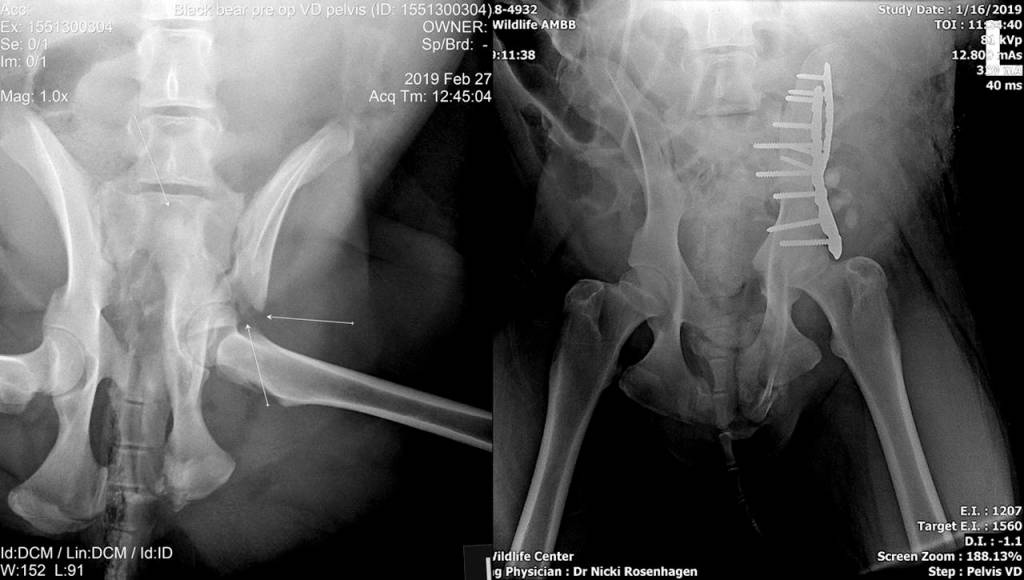

A physical exam and X-rays showed multiple rib and pelvic fractures.

At the zoo, three veterinarians and six veterinary technicians from the different groups monitored the bear’s anesthesia and vital signs. They put the pelvic fragments into alignment with two metal plates and screws, like an orthopedic surgeon would use on a human.

Dr. Tori McKlveen, a Veterinary Specialty Center radiologist, described the post-op X-rays and ultrasound. The bear’s internal organs showed no sign of trauma.